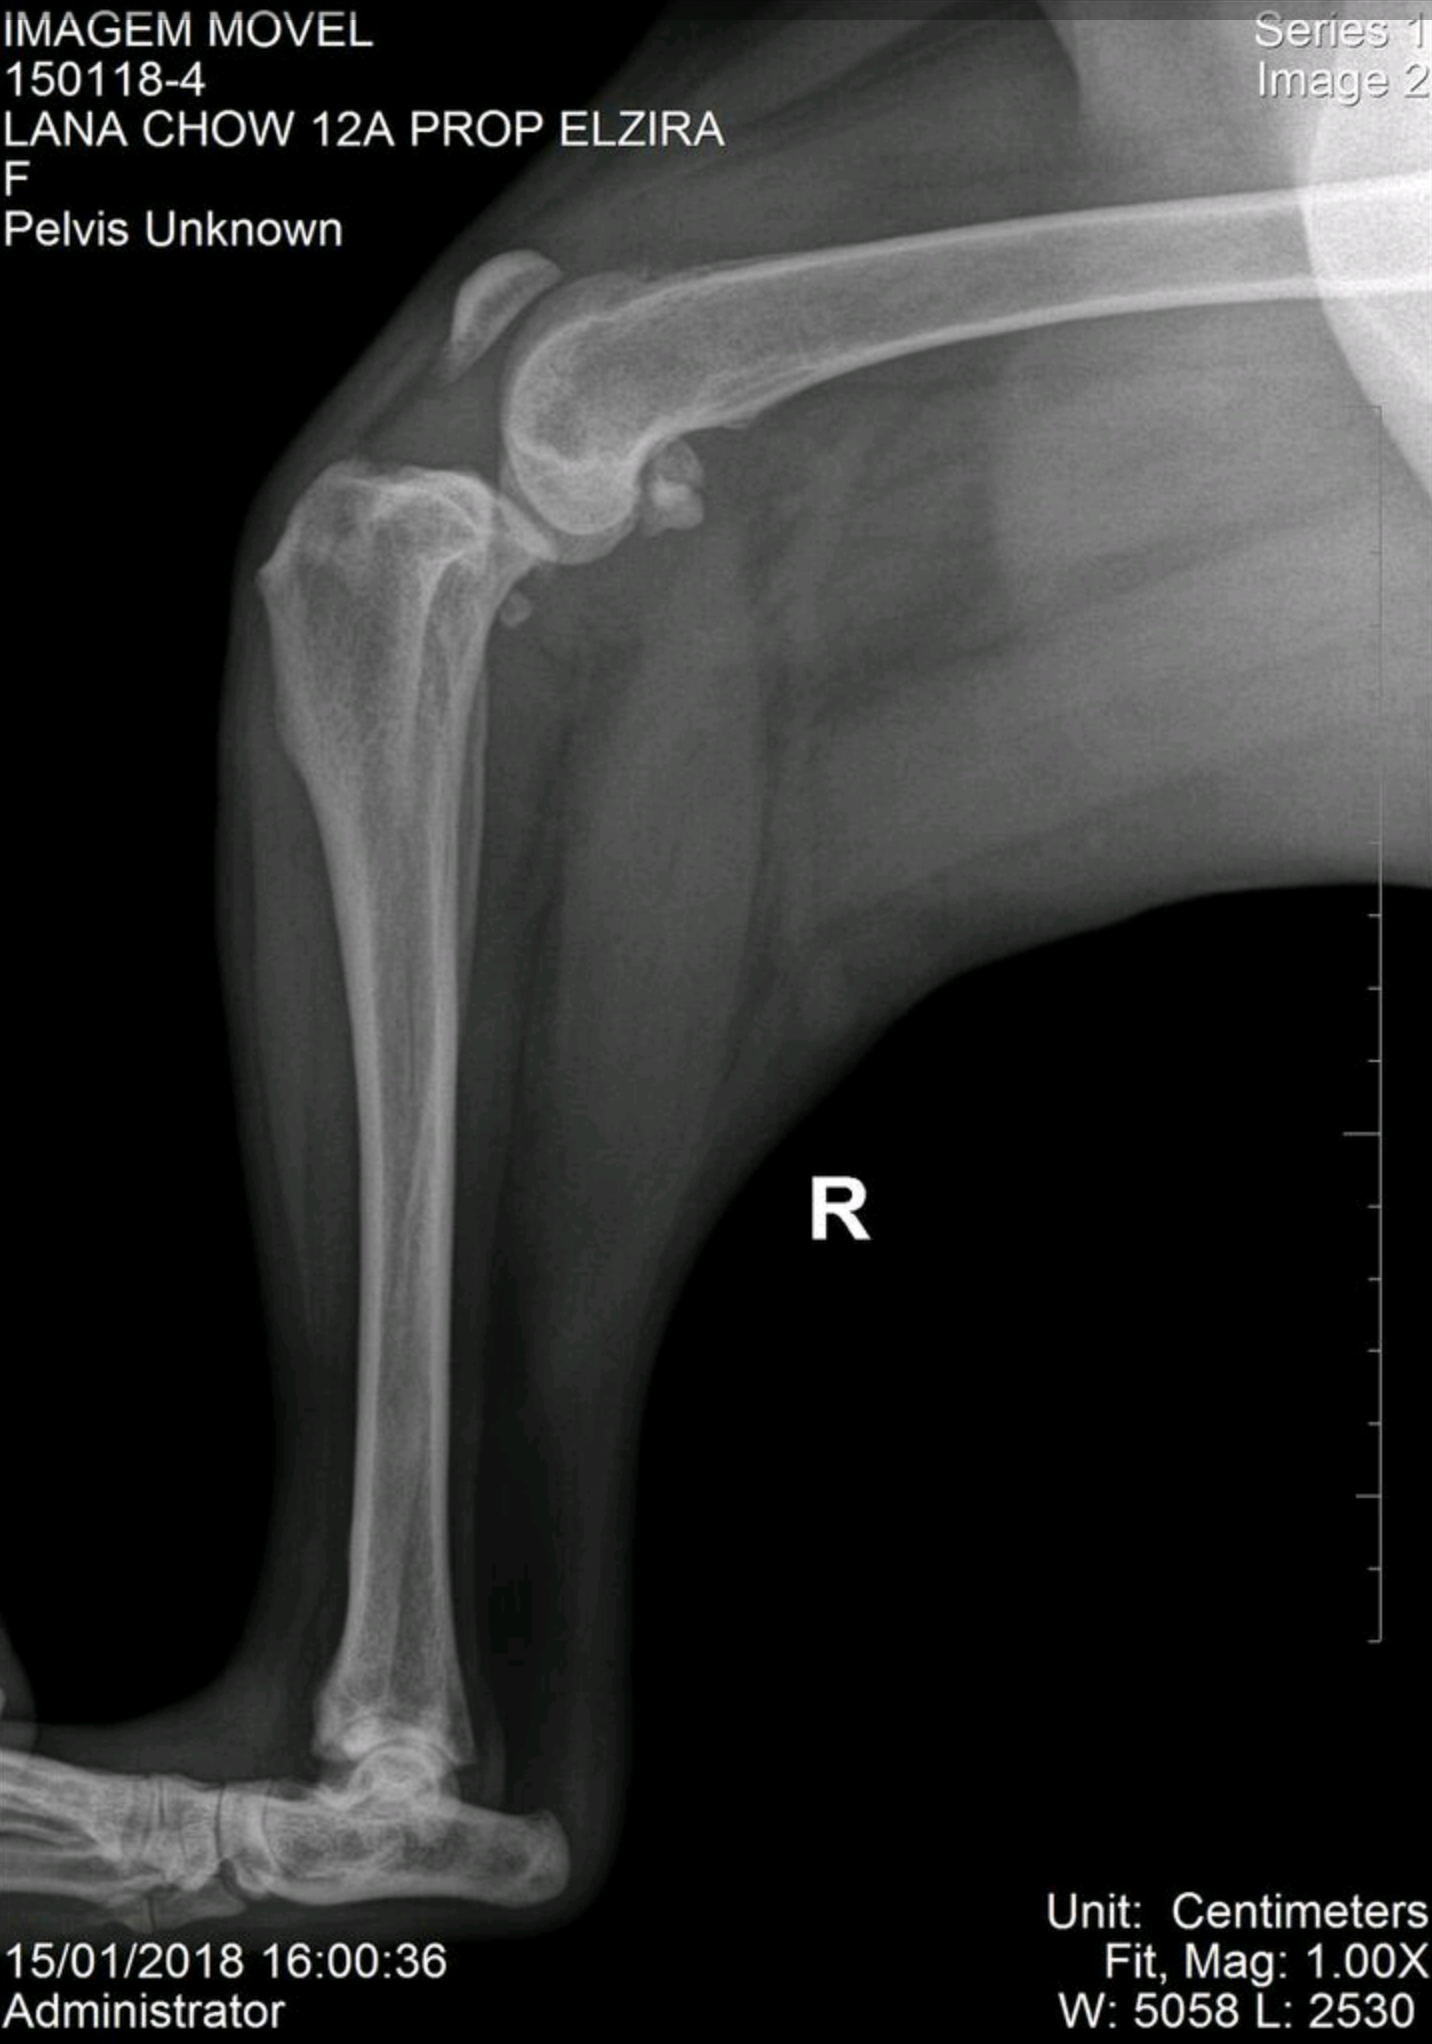

Displasia Coxofemoral em Pastor Alemão

Histórico: Paciente apresentando claudicação progressiva em membros pélvicos.

O Exame: Projeção radiográfica ventrodorsal de coxofemoral.

Desfecho: Diagnóstico de displasia severa; encaminhado para protocolo de manejo de dor e fisioterapia.